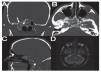

Caso clínico: Varón de 42 años de edad con paresia del VI par craneal derecho y estudios de imagen mediante resonancia magnética y tomografía computarizada craneales sugestivos de displasia fibrosa esfenoclival. Se lleva a cabo un abordaje endonasal expandido transpterigoideo completamente endoscópico, obteniéndose una amplia descompresión de las estructuras vasculonerviosas de la base del cráneo. Durante el procedimiento se utiliza neuronavegación y el canal vidiano como referencia anatómica fundamental de la carótida en su segmento lacerum.

Case report: A 42-year-old male with right sixth cranial nerve palsy. Cranial MRI and CT showed a central skull base lesion with diagnostic suspicion of FD. Patient underwent a full endoscopic transpterygoid EEA, achieving a wide skull base neurovascular decompression. Neuronavigation and the vidian canal landmark resulted mandatory during intraoperative procedure.